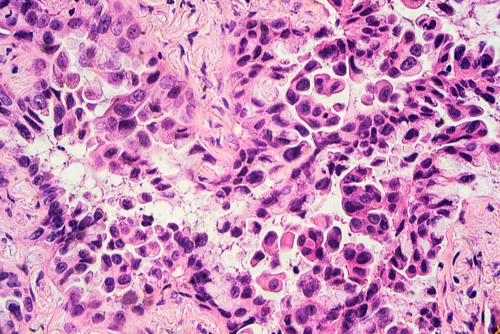

With further development of the devices, a cheap, reusable and accurate breath test for early-stage detection of lung cancer can become a reality, the researchers added in a paper published in the journal Nanoscale. Lung cancer is one of the most common and aggressive cancers, killing around 1.4 million people worldwide each year.